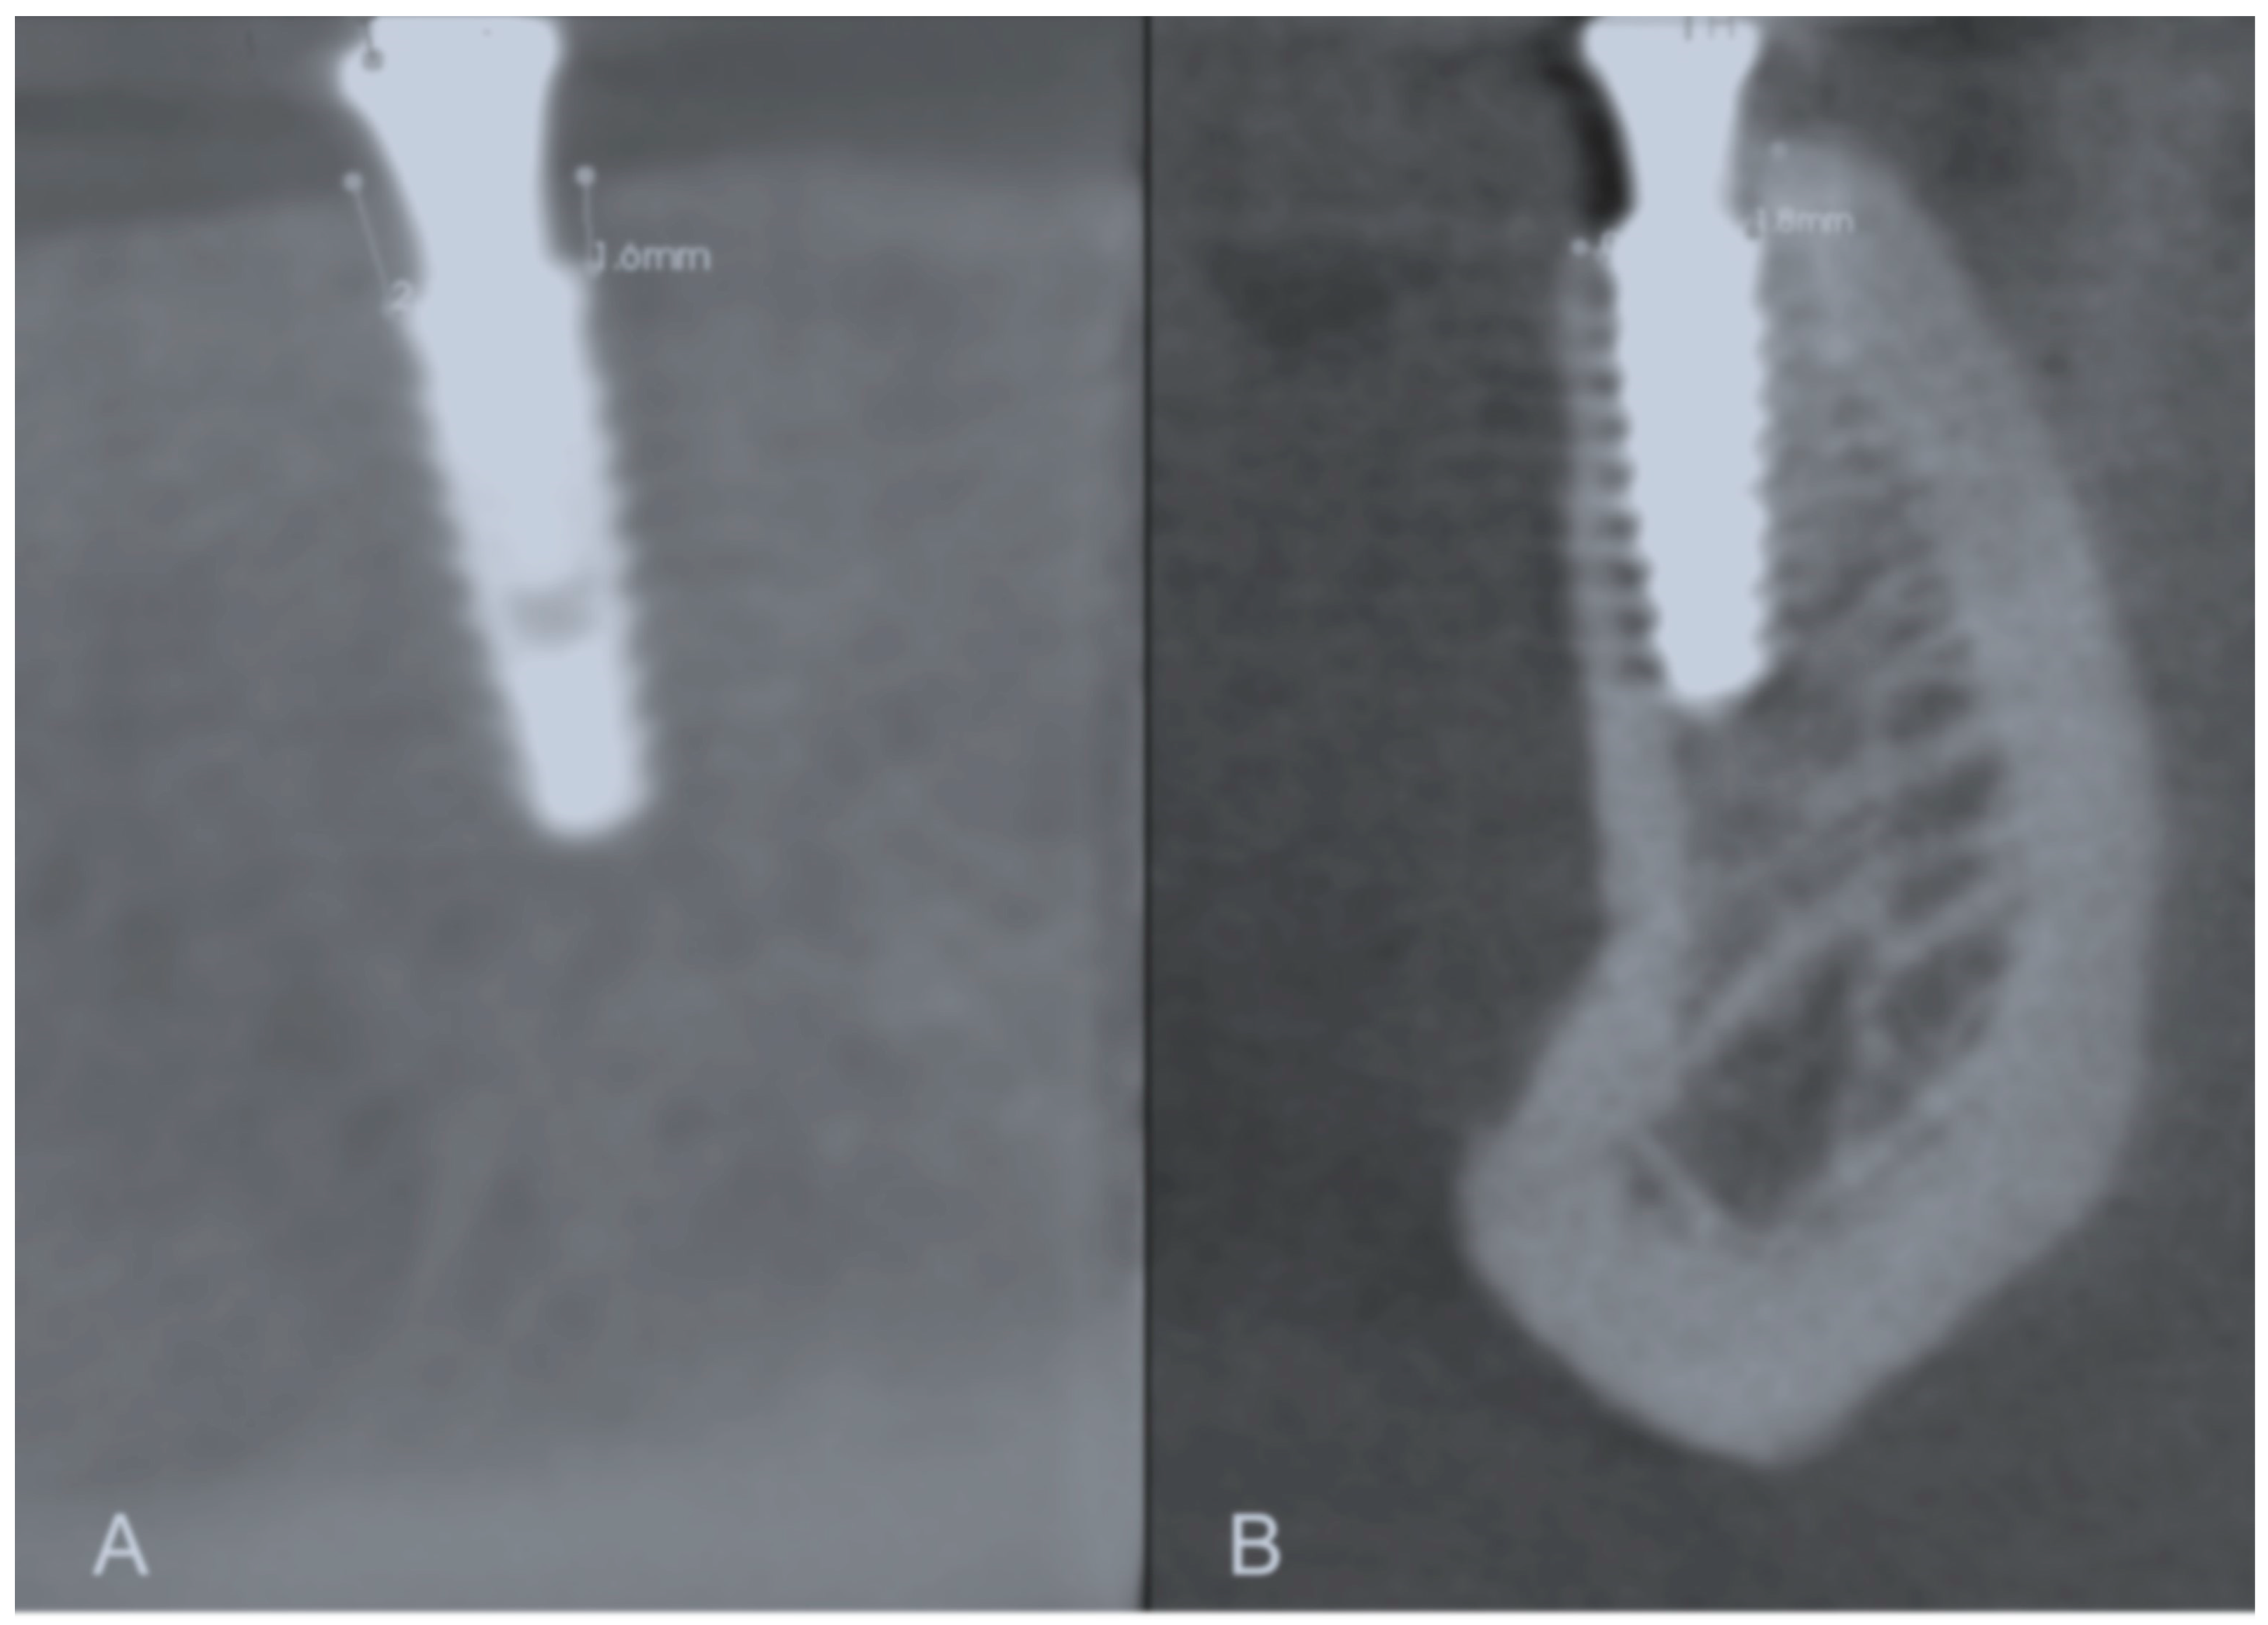

3.3. Tomographic Analysis

| Group | 0–12 Months | 12–24 Months |

|---|---|---|

| Control | 0.74 ± 0.44 Aa | 0.44 ± 0.74 Ba |

| Test | 0.50 ± 0.31 Ab | 0.07 ± 0.15 Bb |

| p-value | 0.0003 | 0.0229 |